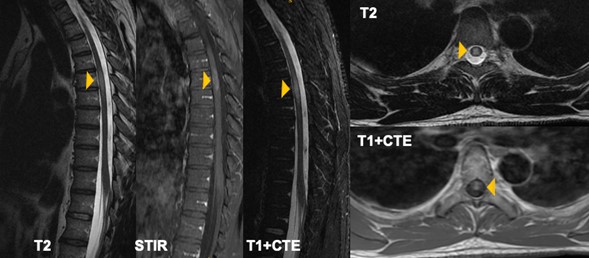

Fig. 2. IRM columna torácica en secuencias T2, STIR y T1 + contraste. Corte sagital y axial a nivel de T5. Hiperseñal en secuencias de T2 intramedular en frente del cuerpo vertebral T5 de localización predominantemente central sin compromiso de la totalidad del diámetro de la médula espinal, asociada a un ligero ensanchamiento y realce homogéneo con el medio de contraste.